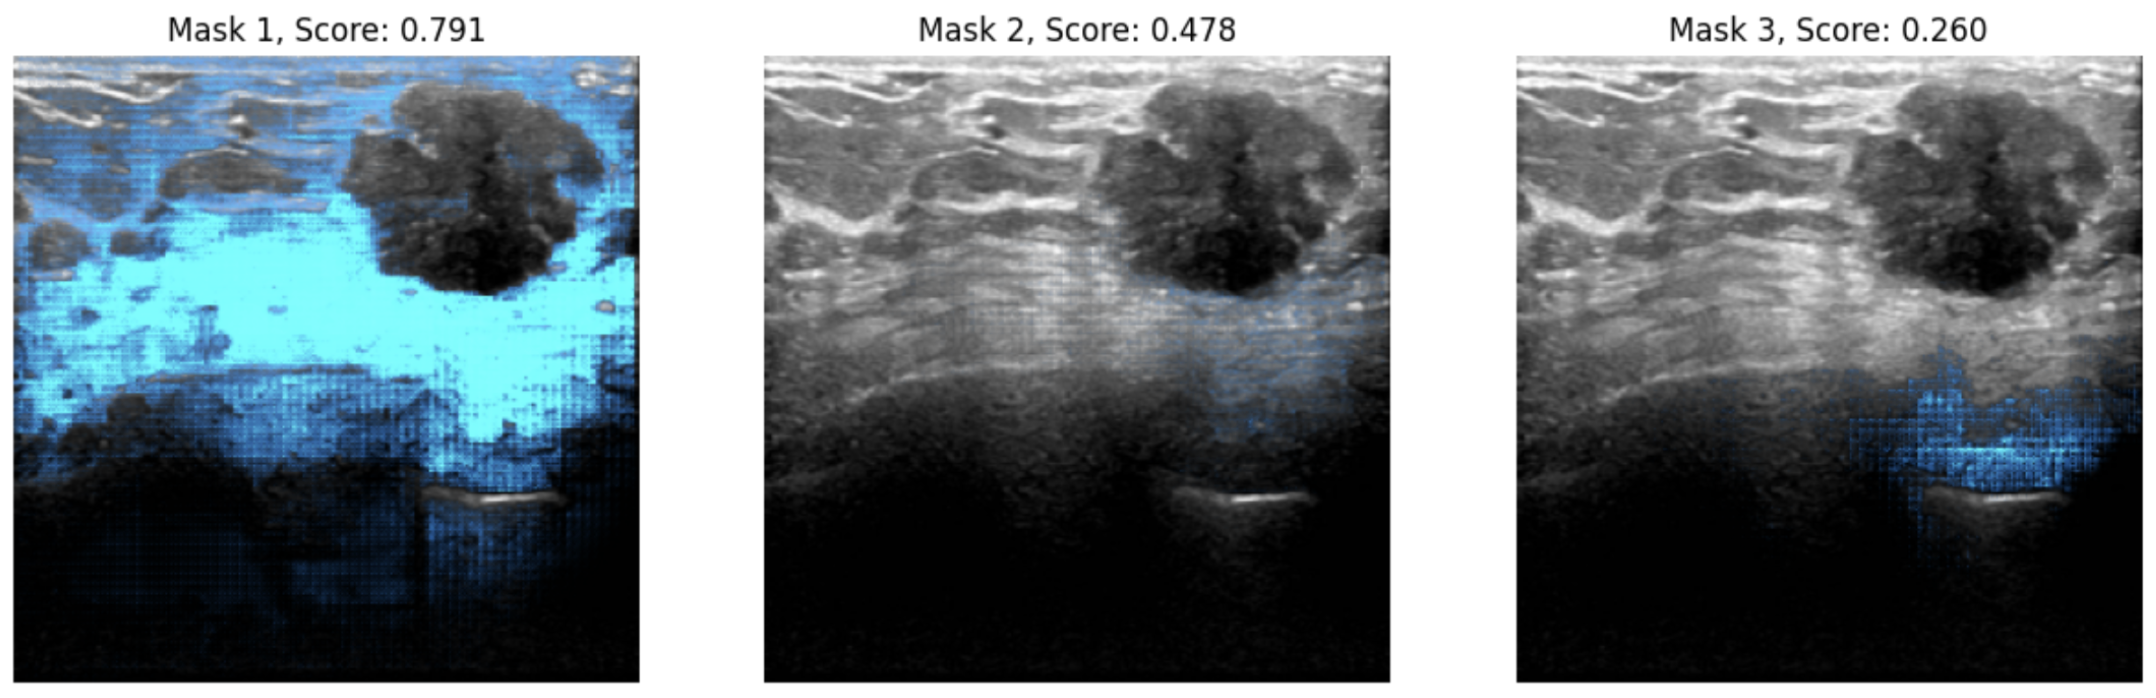

You can see an example inference below.